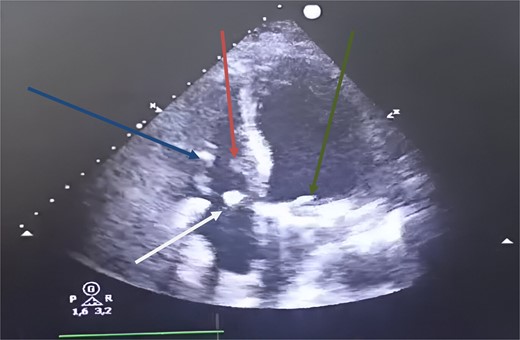

We performed an annular suture, followed by suturing the papillary muscles into the right ventricle: the anterior papillary muscle to the interventricular septum and the posterior papillary muscle to the posterior tricuspid papillary muscle. The repair was consolidated with a tricuspid annuloplasty ring (size 32; Carpentier-Edwards) (Fig. 3). Cultures of the resected segments were negative. Post-operative follow-up was uneventful, and echocardiographic follow-up at discharge showed no residual tricuspid regurgitation or stenosis (Fig. 4).

Postoperative transthoracic echocardiography, four chambers showed at 1 month. Green arrow: mechanical mitral prosthesis in place without stenosis and without detectable leakage. White arrow: tricuspid coaptation without detectable leakage, with slight excess fabric at the suture line on the anterior tricuspid leaflet. Blue arrow: inferior tricuspid papillary muscle. Red arrow: anterior tricuspid papillary muscle.

At the 18-month follow-up, the patient was in NYHA class I, and TTE showed mild tricuspid regurgitation. The mean pulmonary artery pressure had decreased to 18 mmHg.